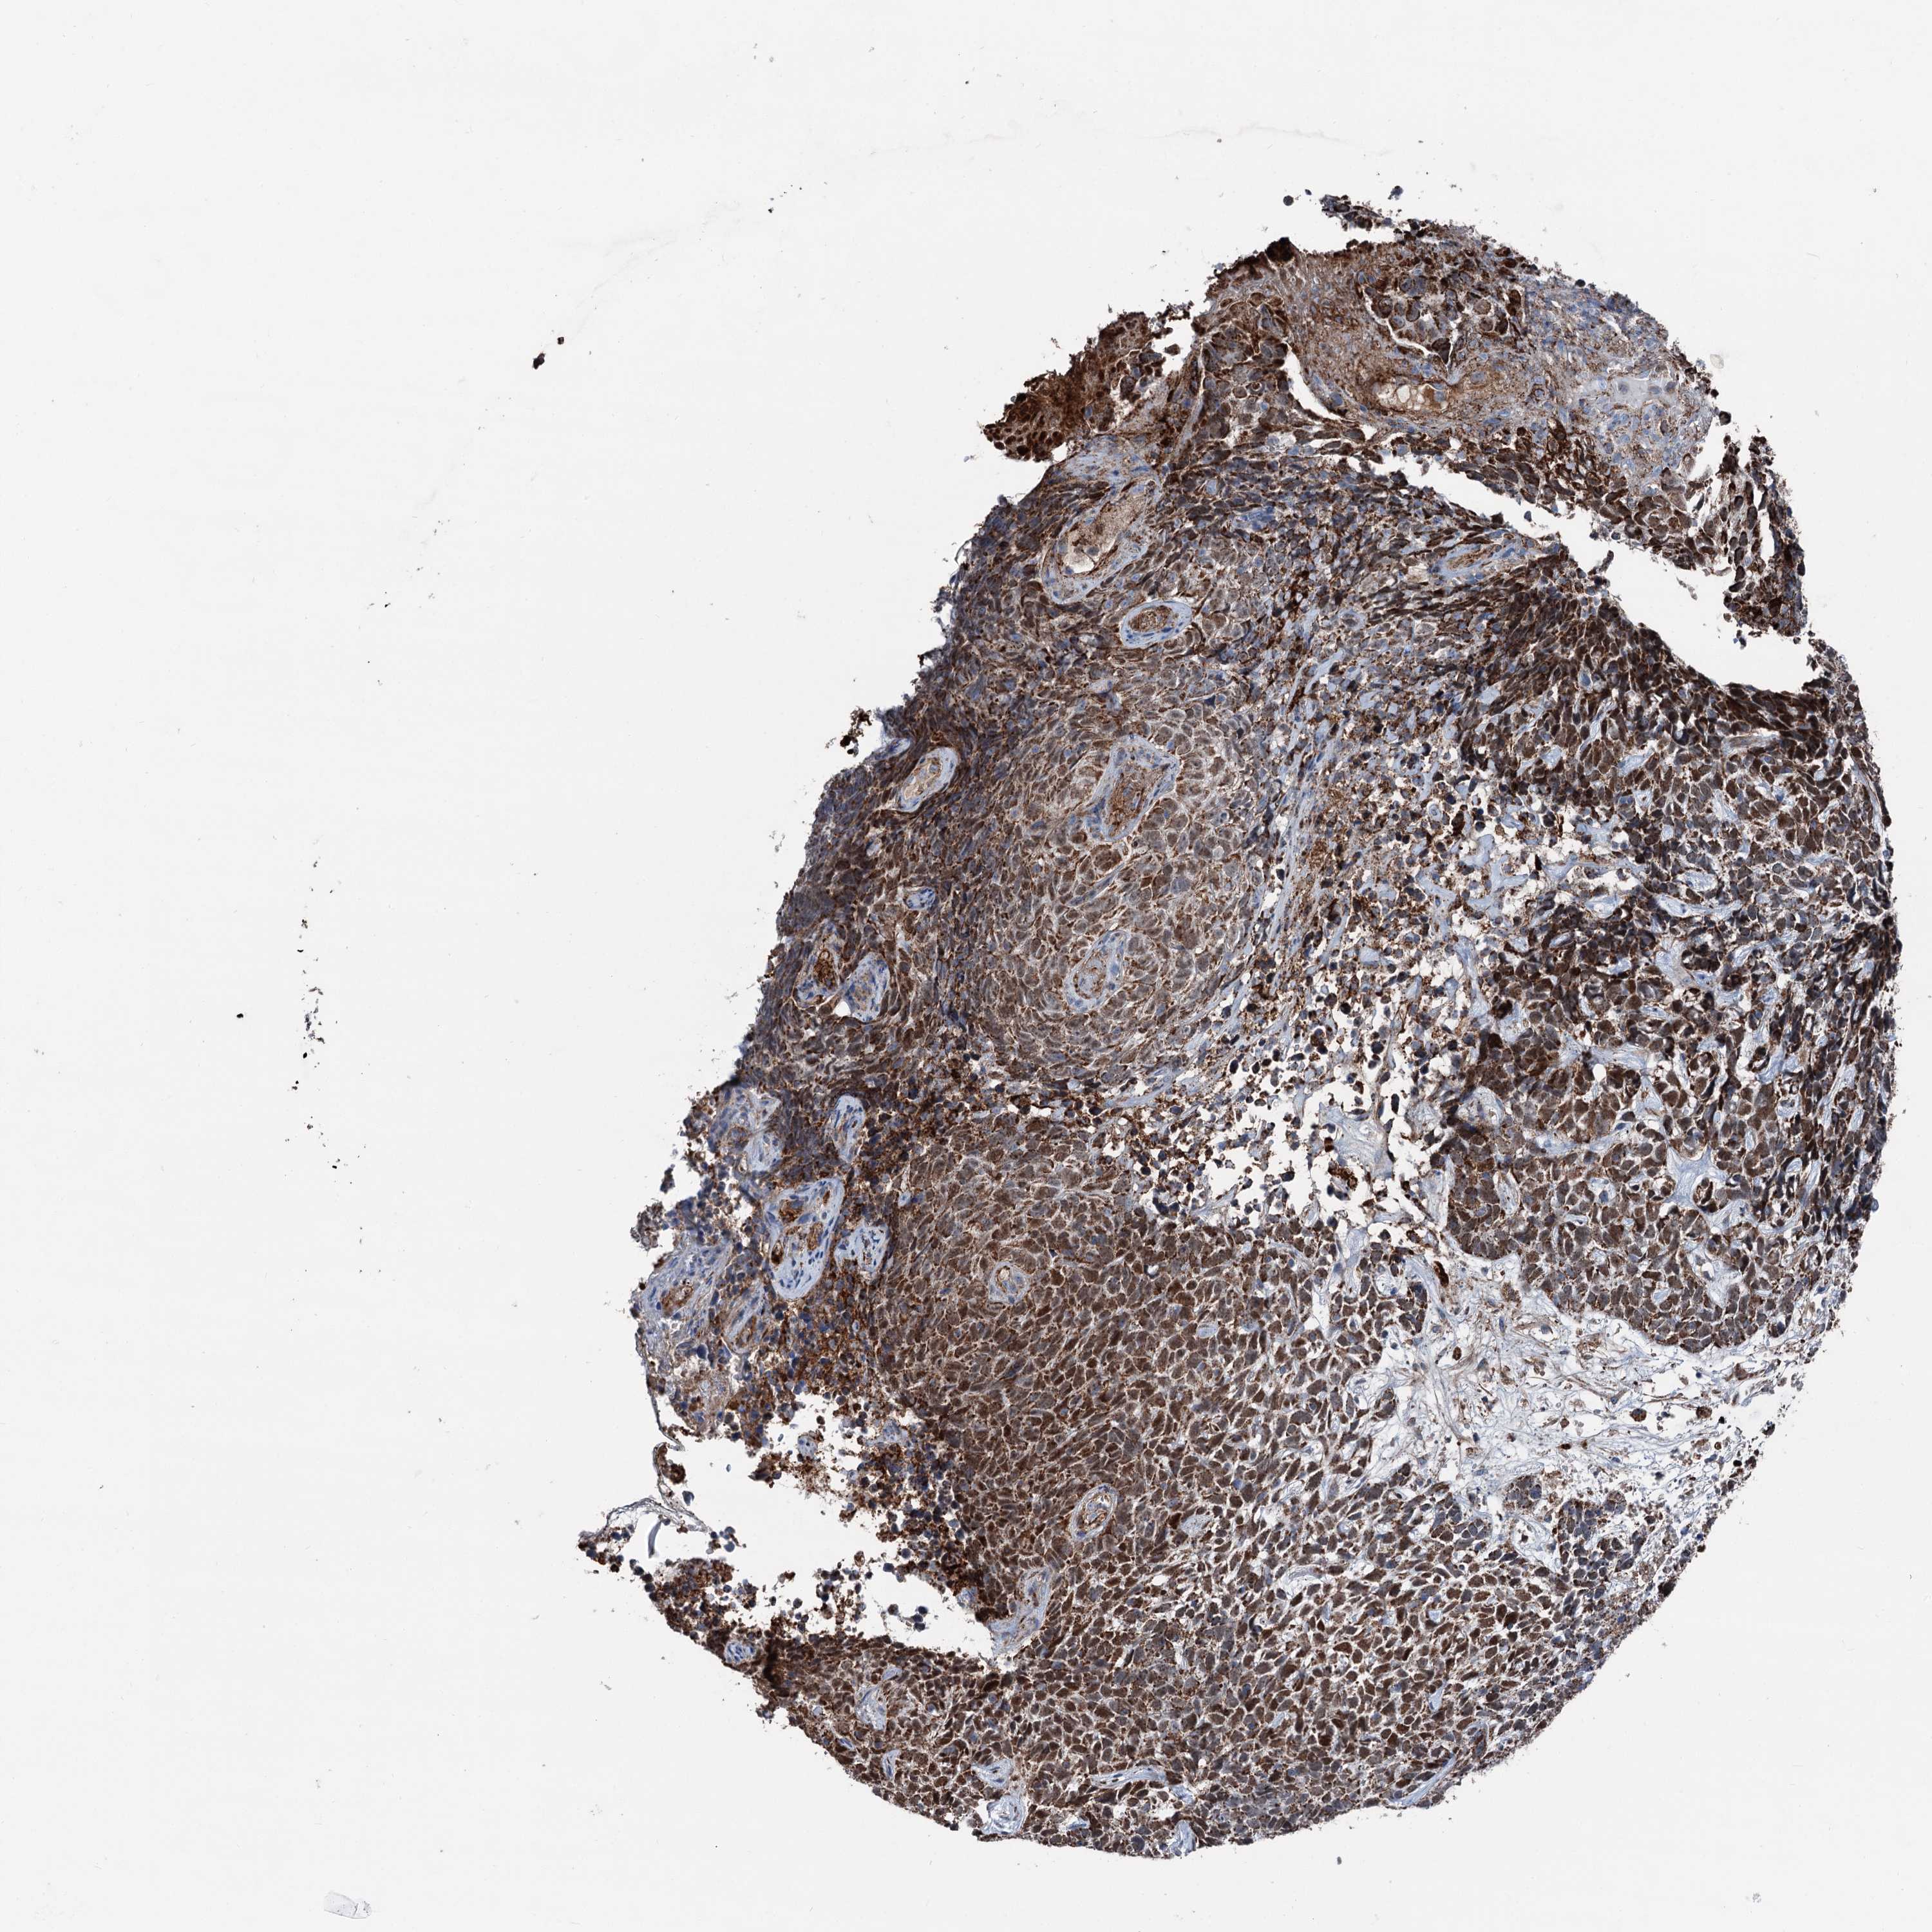

SKIN CANCER - Protein expressioni

A mouse-over function shows sample information and annotation data. Click on an image to view it in a full screen mode. Samples can be filtered based on level of antibody staining by selecting one or several of the following categories: high, medium, low and not detected. The assay and annotation is described here.

Each image is clickable and will lead to virtual microscopy that enables deeper exploration of all samples and also displays staining intensity scores, fraction scores and subcellular localization as well as patient and tissue information for each sample.

Antibody HPA038540

Staining

High

Basal cell carcinoma